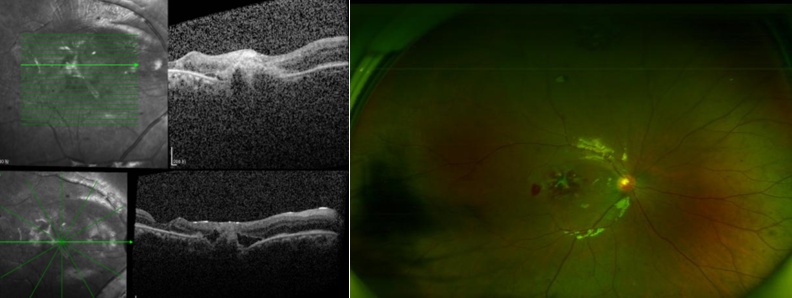

SLO、B超显示右眼玻璃体积血

OCT显示黄斑区巨大裂孔

OCT显示黄斑裂孔逐渐好转,SLO显示玻璃体积血已清除